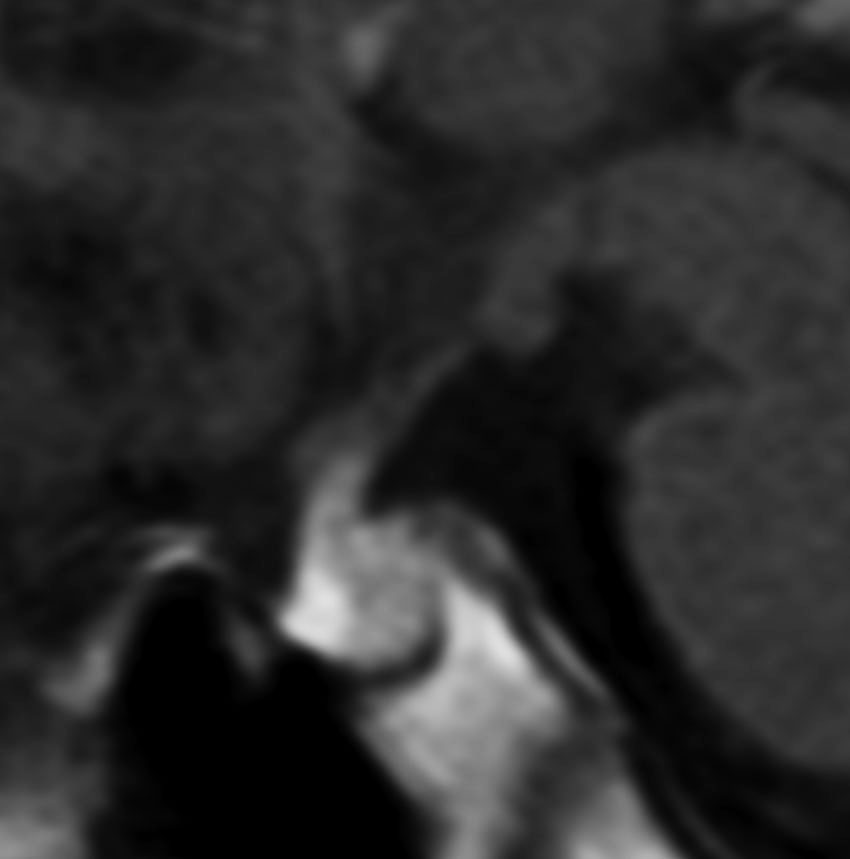

上のMRIで視神経交叉が腫大しているのが解りますが,下のMRI CISS画像では更に明らかです,左右の視神経と視交差と視索が腫大していました。視力を計ったら,右0.6,左1.5でいびつな視野欠損がありました。腫瘍はのう胞形成しながら左の視床下部から大脳基底核にも浸潤していました。

6年以上発ちますが再発はありません。右の画像のように視神経交叉のサイズは正常化しました。下垂体は左に偏っているので,おそらく右側の下垂体にも腫瘍があったのでしょう。汎下垂体機能低下症はありますが,副腎皮質ホルモンの補充は必要なくて,部分的下垂体機能低下症です。この幼児期の低身長が視床下部性であったのか,下垂体前葉機能低下によるものであったのかは不明です。治療後に高ナトリウム血症になる傾向があり,思春期早発症のために成長ホルモンを使用しながらLH-RHアナログを使うという事もしていますから,おそらく視床下部性のGHDであったのでしょう。